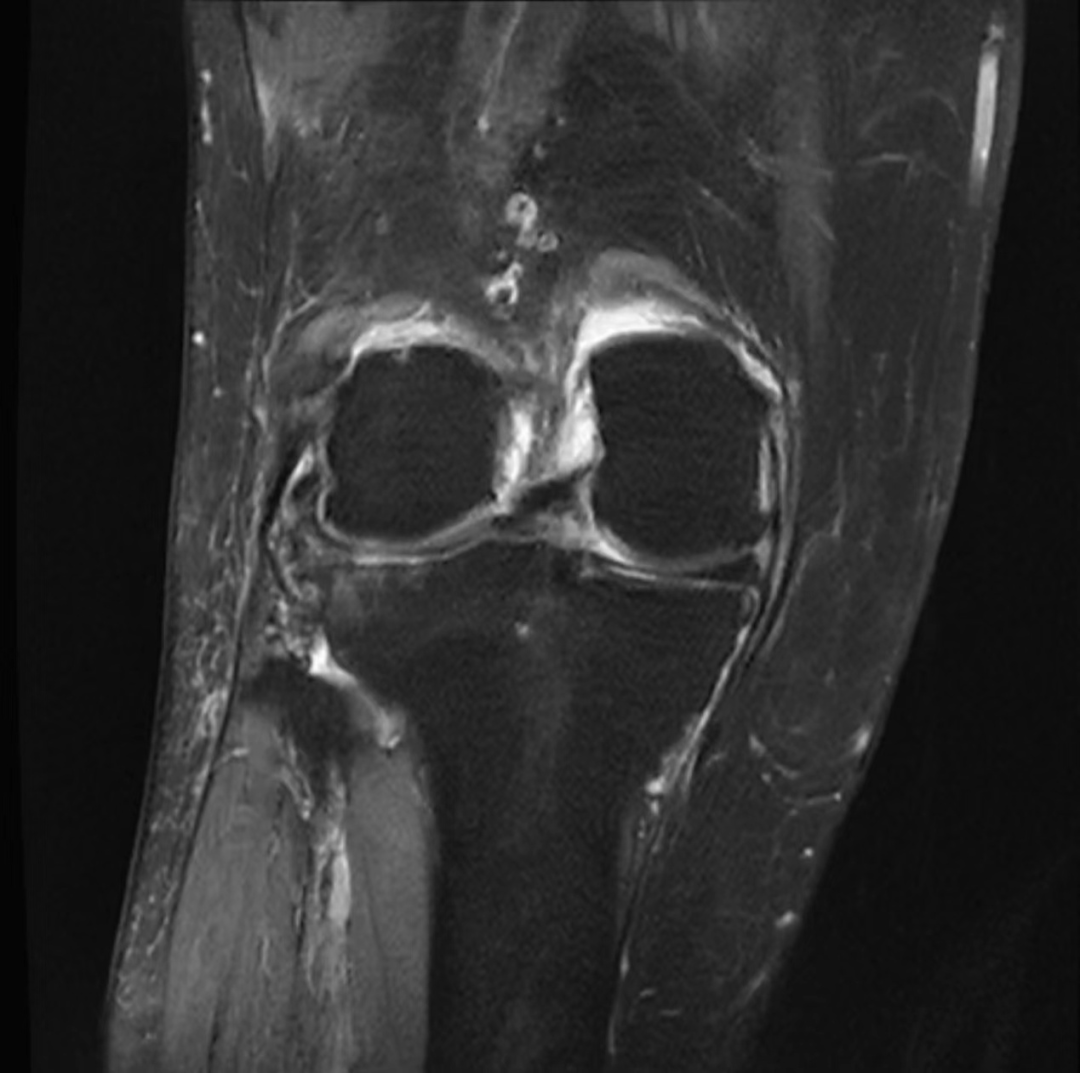

术前核磁共振提示腘窝巨大囊肿

膝关节外侧半月板损伤(III°)